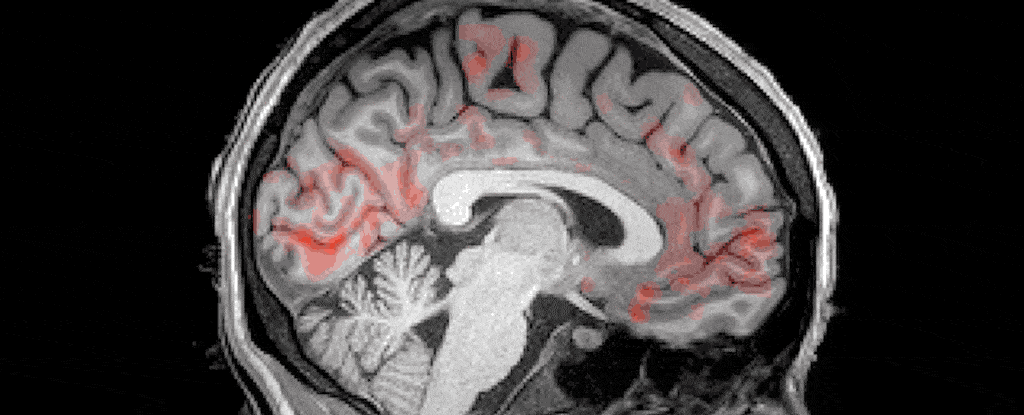

另外,除了在梦里说外语,我们的大脑在夜间还有个特别有趣的地方:每当我们睡觉的时候,大脑会经历一种“洗脑”的过程——对,就是字面意义上的洗脑。你的神经元届时将会变得安静。几秒钟后,血液会流出你的脑部。然后,一种叫做脑脊液(Cerebrospinal fluid)的透明液体将流入,有节奏地“冲洗”你的大脑。

这种新旧知识的融合正是在睡眠中发生的。在白天,我们的海马体负责快速地吸收信息,像海绵一样吸收新的单词。而到了夜晚,它将这些新获得的信息转移到大脑的其他区域,而在这些区域它能被储存并与其他相关信息相互连结[7]。这种储存形式能够帮助我们在任意情况下选择正确的措辞,并抑制与其相冲的词语。

这将会是个非常棒的解释,但可惜的是,整合巩固的过程发生在我们所谓的深度睡眠阶段,或慢波睡眠阶段。这一阶段的特征[8]是慢脑波以及更高频率的纺锤波(纺锤波是在非快速眼动期每隔几秒出现的高频爆发,译者注)。而复杂的梦境,比如我的酒店梦境,更倾向在另一个阶段发生,即快速眼动(REM)期。

至关重要的是,这两个单词(“tofer”,和搭配的德语单词)都必须在慢波睡眠阶段播放,更确切地说,必须在慢波睡眠的峰值时刻。一旦研究员错过了峰值,词义匹配就会失去效果。

脑电图结果显示[9],熟睡受试者的大脑更倾向于关注于有意义的语音片段,而不是伪造的。然而,在梦境频发的快速眼动期,受试者则更倾向于关闭或抑制外来的语音输入。科罗马猜测这或许是因为大脑在快速眼动期更专注于内部的信息处理:“当我们沉浸在梦境中时,任何有可能搅动梦境的事物都会被拒绝。”